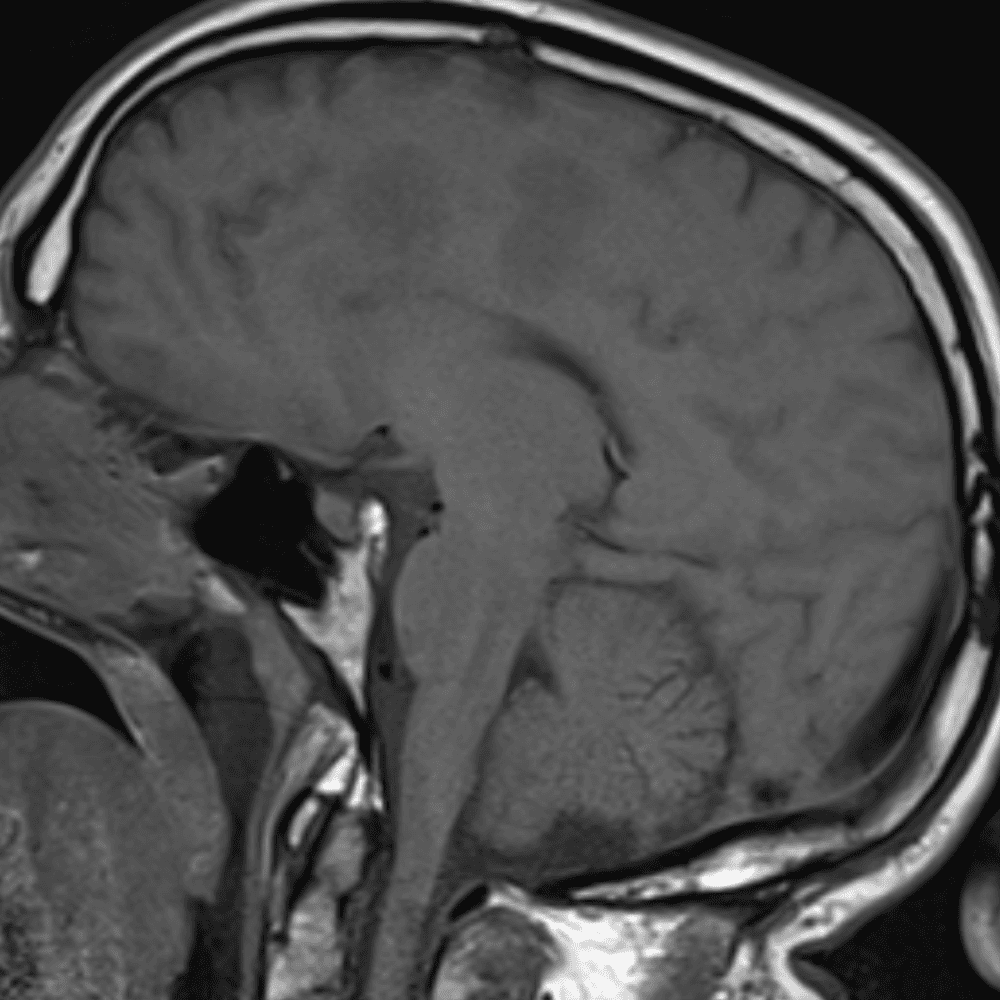

์—ฐ์Šต

๋ฏธ๋ฌ˜ํ•˜๊ฑฐ๋‚˜ ์–ด๋ ค์šด ์‚ฌ๋ก€์™€ ์ผ๋ถ€ ์ •์ƒ ์‚ฌ๋ก€๋ฅผ ํฌํ•จํ•˜์—ฌ ๋‹น์ง์„ ์‹œ๋ฎฌ๋ ˆ์ด์…˜ํ•ฉ๋‹ˆ๋‹ค.

50 ์‚ฌ๋ก€